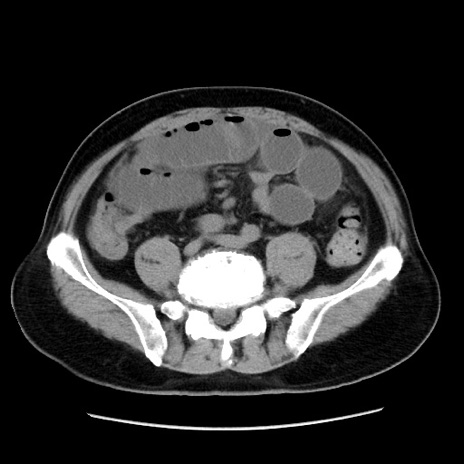

症例16(横断像)

冠状断像

【症例】 70歳代男性

【主訴】 腹痛、嘔吐

【現病歴】 約1ヶ月前より間欠的に腹痛と嘔吐あり、当院消化器内科を受診したところCTで多発する肝臓のLDAを指摘され、精査中であった。以降は消化器症状は安定していたが、2日前より嘔気と腹痛があり、同日より排便・排ガスが消失した。改善認めず、 本日、救急外来を受診した。

【既往歴】 大腸ポリープ切除後。

【身体所見】意識清明・会話良好、BT 36.3℃、BP 127/80mmHg、 P 80bpm、腹部:膨満あり、平坦・軟、上腹部正中および下腹部正中に圧痛あり、反跳痛なし、筋性防御なし。

【データ】WBC 7200、CRP 0.77